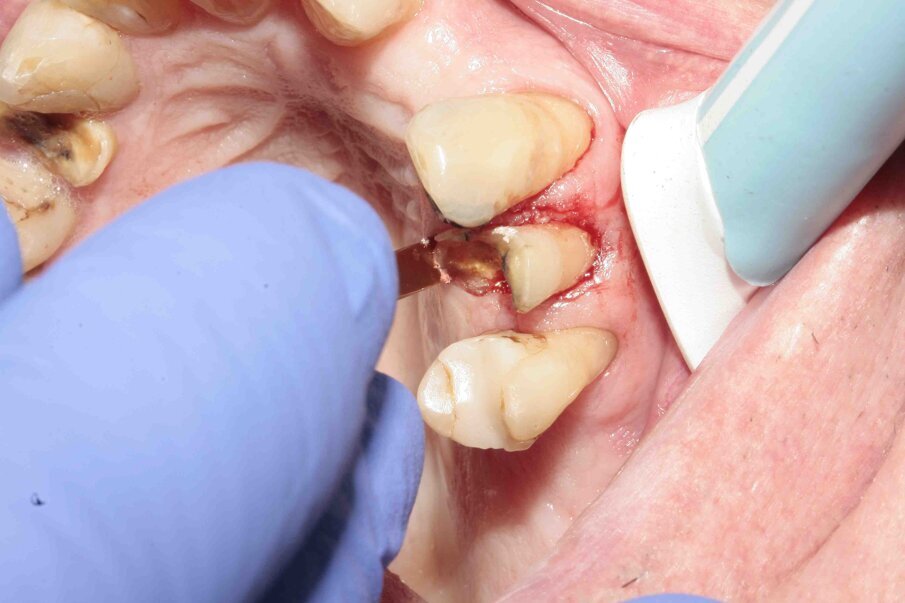

Fig. 9: During luxation, the palatal root was partially fractured while in the alveolus.

Figs. 10–12: The fractured root was carefully luxated with Luxator P1 and Luxator L3S.